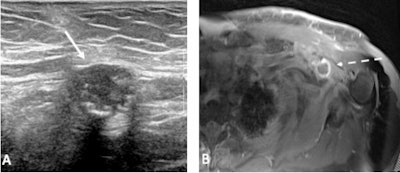

"Similarly, on CT the nodes may be enlarged with thickened cortices and possibly with surrounding fat stranding," Brown and colleagues pointed out. "A feature unique to MRI in determining vaccination as the cause of axillary adenopathy is high T2/STIR signal in the ipsilateral deltoid muscle corresponding to the injection site."

"There are also several benign findings that can be found in the axilla that may resemble a reactive lymph node. For example, paralabral cysts are often associated with labral tears and can cause pain, weakness, and denervation of the supraspinatus and infraspinatus muscles secondary to nerve compression. These are benign and biopsy is not recommended for confirmation," Chan and Fischer wrote.

Another important benign entity to distinguish are venous malformations, up to 40% of which are located in the extremities. Recognizing a potential vascular malformation in the axilla will prevent unnecessary biopsy, which would cause significant bleeding.